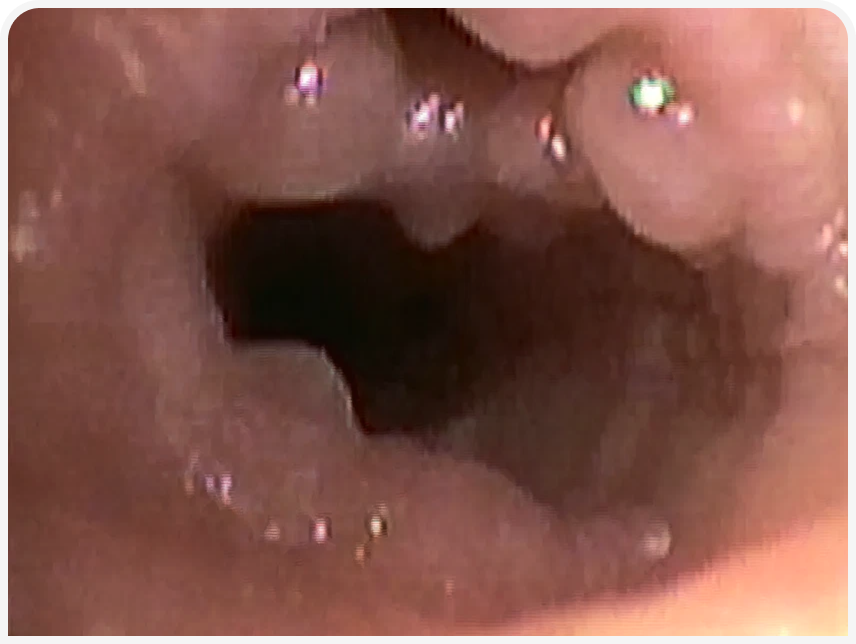

Подтвердить коллапс трахеи и дыхательных путей и оценить тяжесть заболевания можно с помощью бронхоскопии (Рисунок 4). Вероятно, этот метод лучше всего позволяет диагностировать бронхомаляцию сегментов нескольких долей (Рисунок 5), а также подтвердить динамический характер заболевания при поражении небольших сегментов дыхательных путей.

Бронхоскопия также позволяет выявить бронхоэктазы (Рисунок 6) или другие необратимые изменения, такие как бронхитические узелки или воспалительные разрастания в дыхательных путях (Рисунок 7).